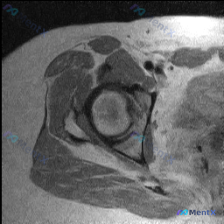

最近整理到一个髋关节MRI影像分析的病例,患者临床怀疑盂唇病变,但提供的单张T1轴位片未显示明确异常。报告详细分析了解剖结构、病变可能性、诊断路径等内容,其中有几个点比较值得讨论: 1. 单张T1轴位片对盂唇病变的敏感性如何? 2. 影像阴性但临床高度怀疑时,下一步应如何评估? 3. 盂唇病变的诊断...

看到一个髋关节MRI评估病例,患者因髋部症状(疼痛、弹响等)行检查,目前只提供了T1轴位序列图像。图像显示盂唇形态完整、信号连续,未见撕裂、退变等明显病理改变。但T1序列存在局限性,对细微损伤不敏感。 大家怎么看这个病例?您认为盂唇病变的可能性大吗?需要进一步做哪些检查?